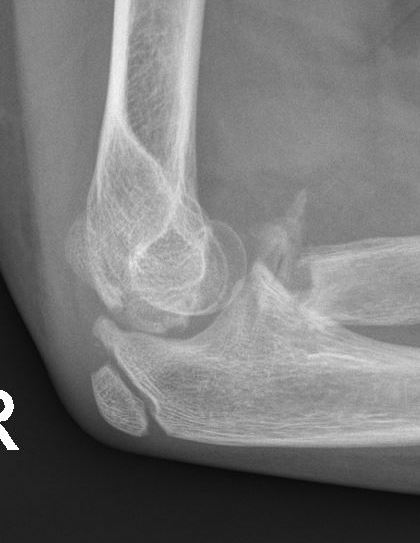

Radial neck fracture and olecranon fracture